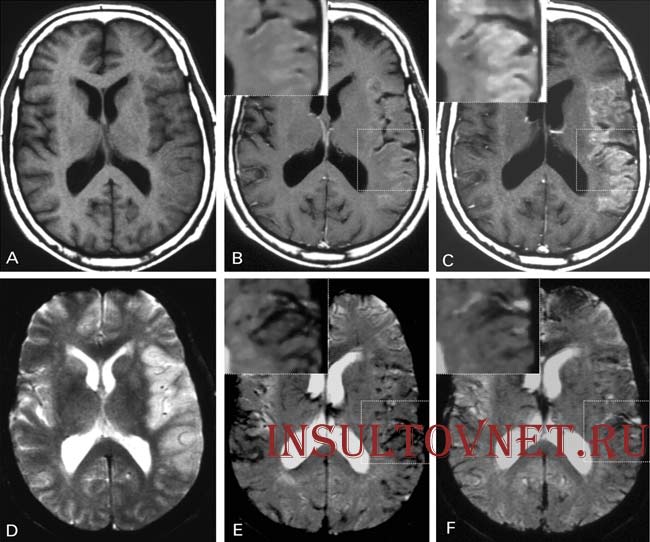

В медицине существуют два метода, с помощью которых есть вероятность определить точное место, где именно произошло кровоизлияние в мозг – это магнитно резонансная томография, что позволяет диагностировать мозг изнутри и выявить патологию на ранних стадиях. И второй метод это спиральная или компьютерная томография. И первый и второй способ направлены на изучение внутренней полости полушарий мозга пациентов, страдающих кровоизлиянием в мозг, то насколько кровь глубоко успела проникнуть в желудочек. Что также необходимо проводить в профилактических целях до или после заболевания.

Что также позволяет сделать соответствующие выводы по поводу возникших признаков гематомы, так как повлиять на ее образование могут и другие факторы имеющих схожую симптоматику с геморрагическим инсультом. Иногда кровоизлиянием могут страдать люди, страдающие менингитом. Именно эти симптомы внешне чем-то могут иметь общие черты с геморрагическим заболеванием кровеносных сосудов головного мозга.